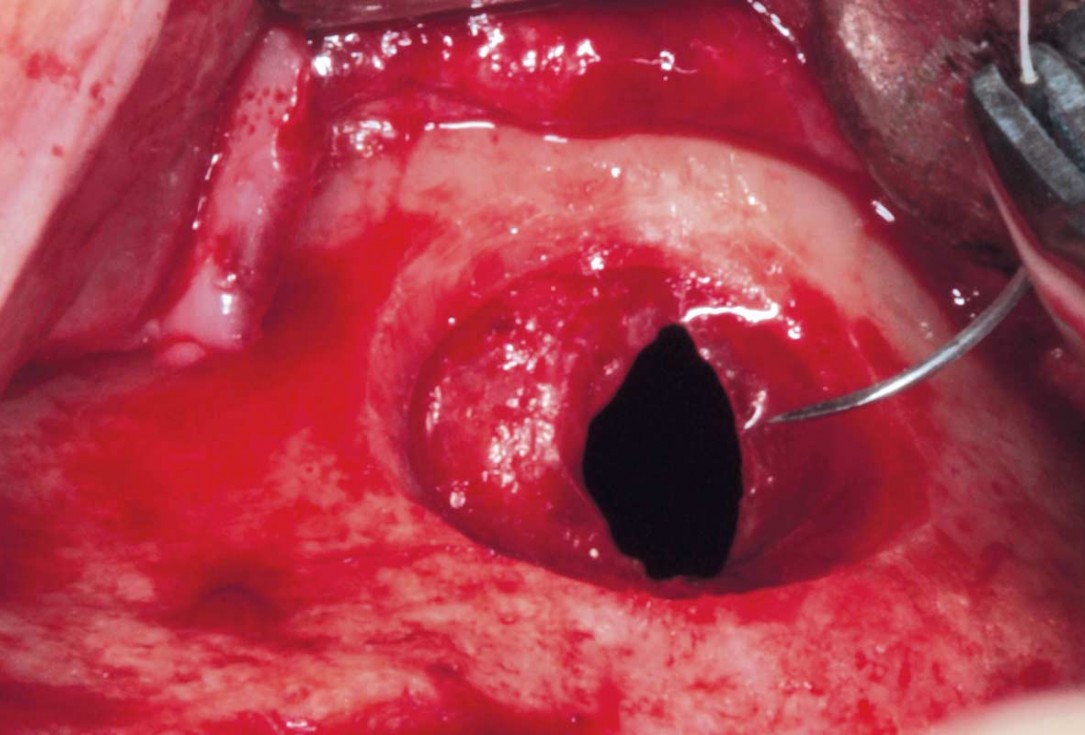

05/35 - Detached sinus membraneMaxillary sinus cyst removal using the Crocodile Technique and subsequent lateral sinus lift - Dres. C. Scognamiglio and A. Perucchi